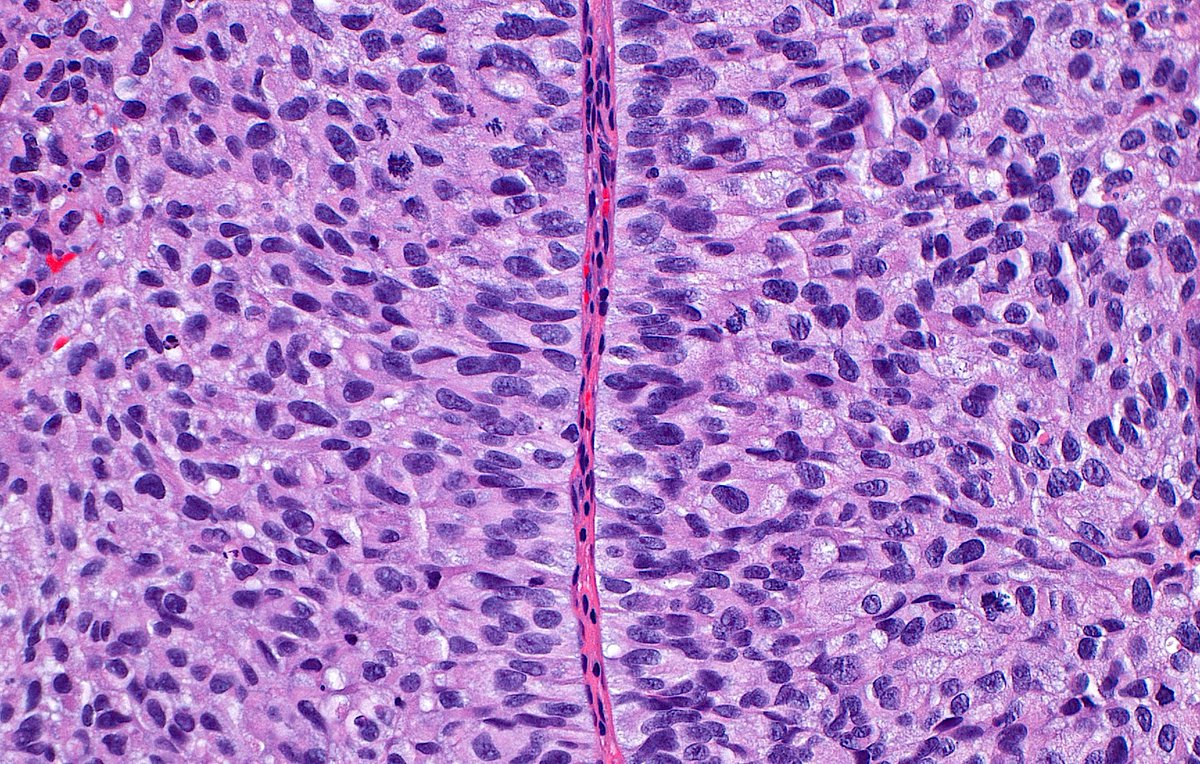

"Edge of destruction" ~ Interface between necrotic (right) and viable (left) liver in a patient treated for hepatocellular carcinoma. #pathology #pathart #liver #liverpathology #hepatology #oncology